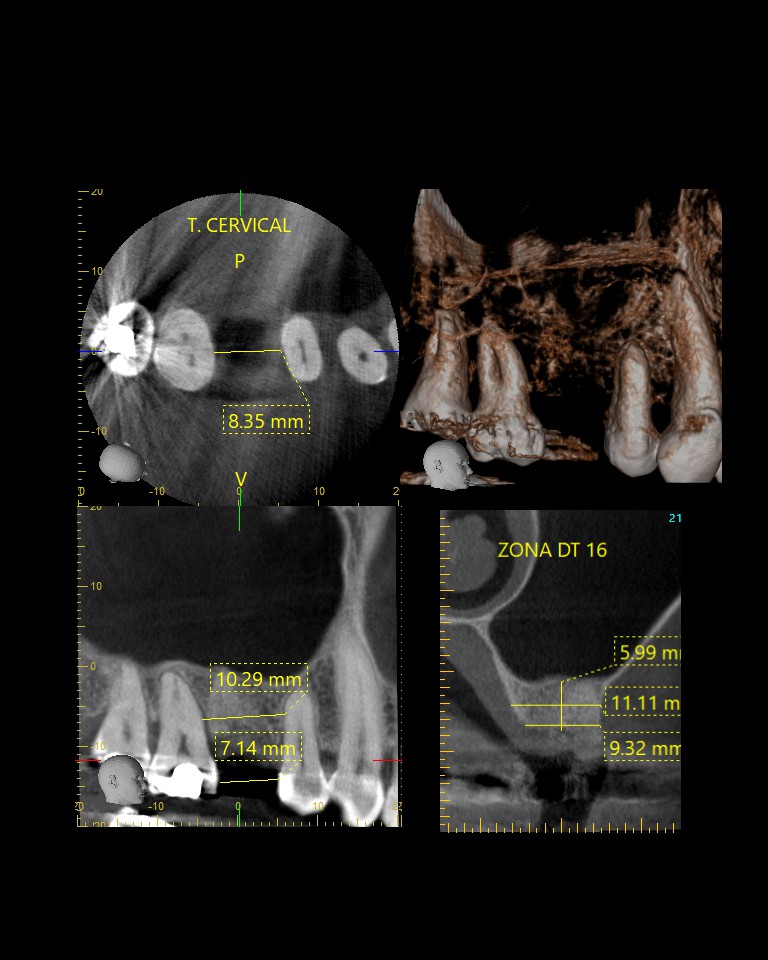

- CBCT: La tomografía computarizada de haz cónico es una imagen en 3D que proporciona imágenes de alta resolución del complejo craneofacial. Permite evaluar la cantidad y calidad ósea para la colocación de implantes dentales, adicionalmente es útil para la evaluación de dientes incluidos, fracturas y reabsorciones radiculares, entre otros.

La tomografía computarizada de haz cónico (CBCT) proporciona imágenes en 3D de alta resolución del craneofacial, ideal para planificar implantes, evaluar dientes incluidos, fracturas y reabsorciones radiculares.